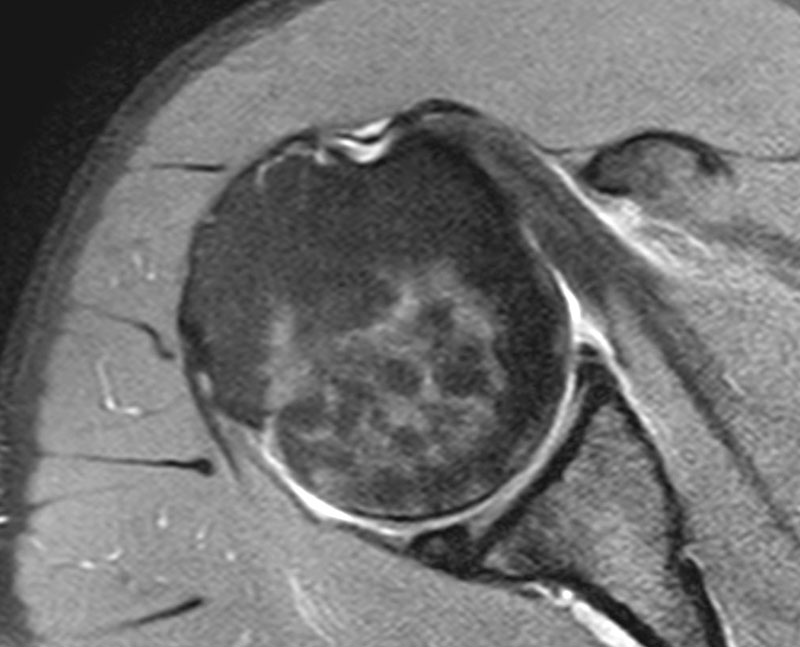

MedView Medical Imaging Consultancy Info Page Calcific bursitis Theragun For Hip Bursitis physical therapy can help with trochanteric bursitis by strengthening the muscles of the hip and improving alignment of the pelvis to. learn about the causes, symptoms and treatment of outer hip and thigh pain, also known as trochanteric bursitis. treat your pulled muscle with the price method (protection, rest, ice, compression, elevation) and see a doctor if. Theragun For Hip Bursitis.